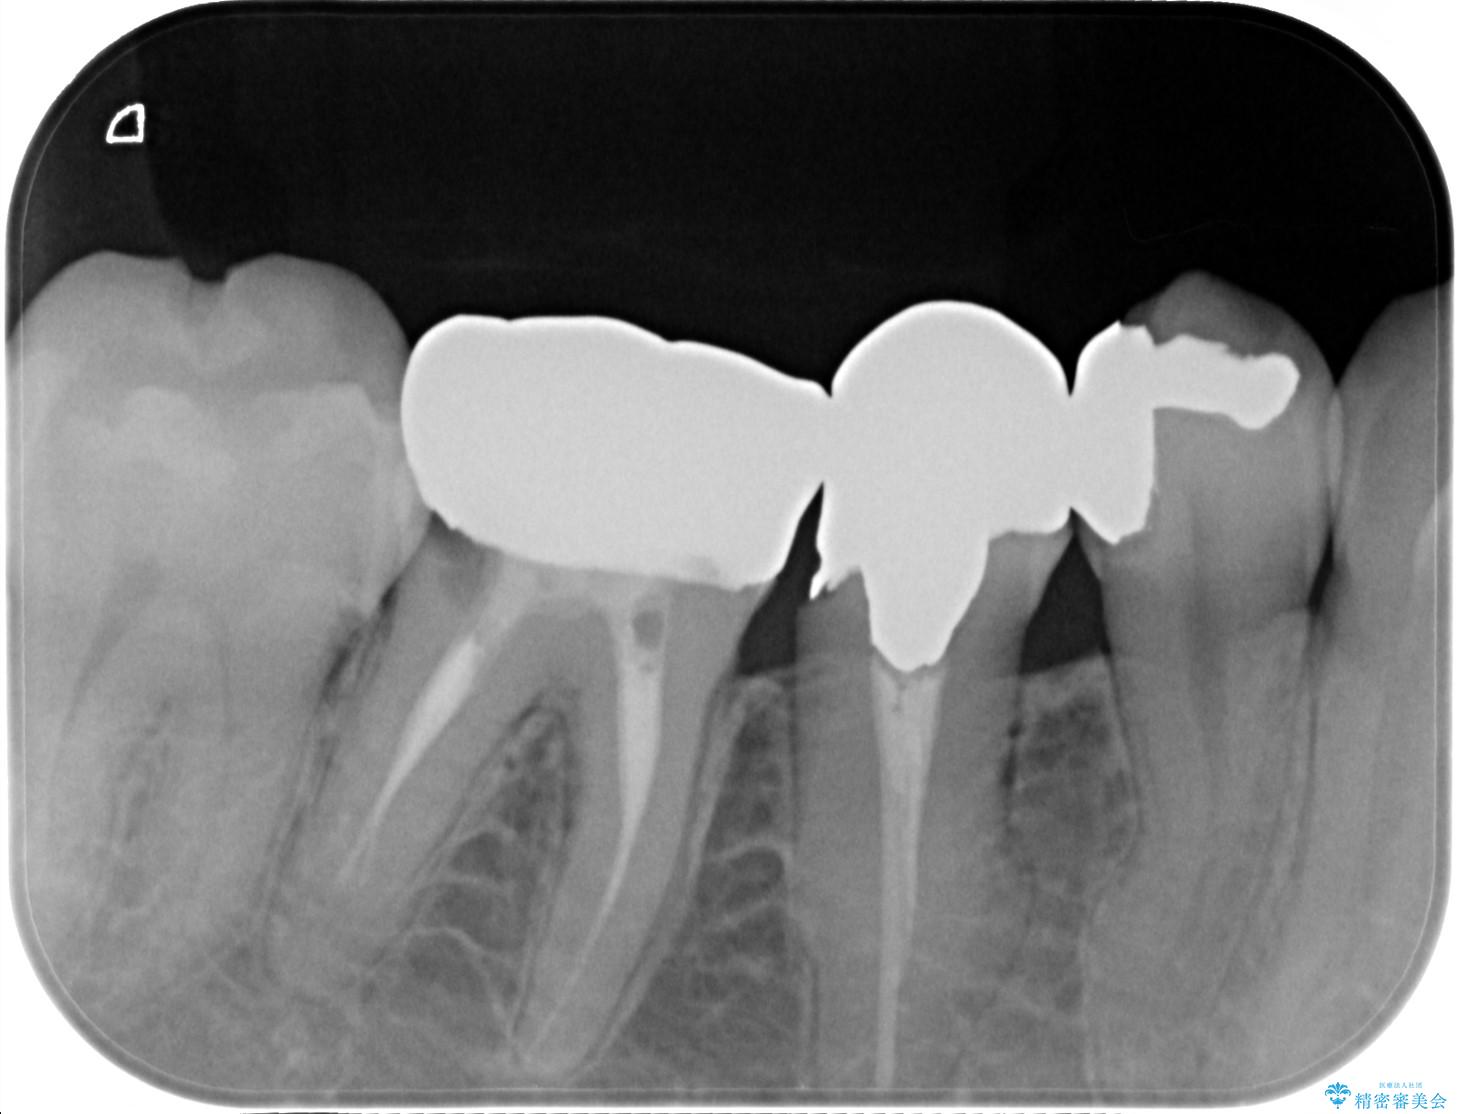

装着されていた清掃性の悪い銀歯を外すと、銀歯の下で歯ぐきよりも深い虫歯が再発していました。

虫歯を丁寧に除去し、歯周外科を用いて周囲の歯ぐきの炎症を除去します。その後、清掃性の高い精密なセラミック治療をおこなっていきます。